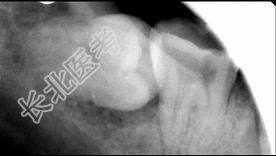

- 多项选择题关于阻生牙阻力来源正确的是 ( )

A、阻力来源于邻牙

B、阻力来源于骨组织

C、阻力来源于牙龈

D、阻力来源于咀嚼肌

E、阻力来源于对

牙